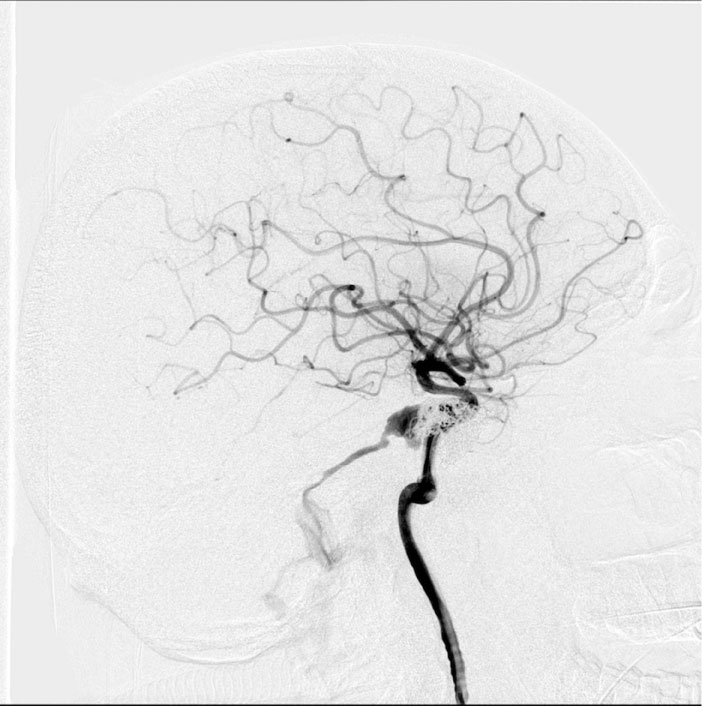

In order to determine further treatment tactics, the patient underwent selective cerebral angiography: According to the selective cerebral angiography data, a type A carotid-cavernous fistula was revealed (Figure 2).

Figure 2: Angiography of the internal carotid arteries (ICA), lateral projection: Carotid-cavernous fistula of the right ICA with discharge into the upper stony sinus. Condition after previous embolization. View Figure 2